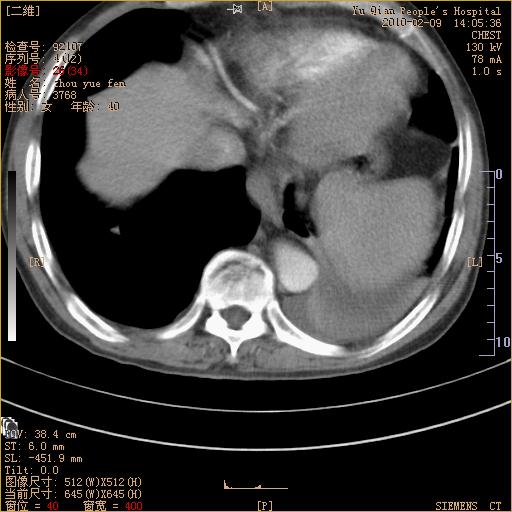

男性,73岁,咳嗽咳血数天,诊为肺ca伴左肺下叶后段阻塞性炎症、肺不张妥否?

左下肺中央型肺癌伴结段形肺不张,左侧胸腔积液,纵隔内见部分增大淋巴结(反应性增生或转移)

左下基底干支气管明显变窄。

左肺下叶基底段支气管狭窄,左肺门增大,左肺下叶团片状病灶。中心型肺癌伴柱塞性炎症可能大,建议支气管镜检查。

左下肺中央型肺癌伴节段性肺不张,左侧胸腔积液,纵隔内见肿大淋巴结

左下基底段支气管变窄。建议进一步纤支镜检查。

1、左肺下叶后基地段肺癌伴阻塞性炎症,左下肺门淋巴结转移。2、左侧胸腔积液。